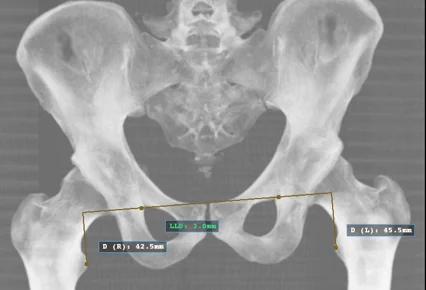

Most of us assume that our legs are the same length — after all, why wouldn’t they be? But in reality, many people (over 75%)